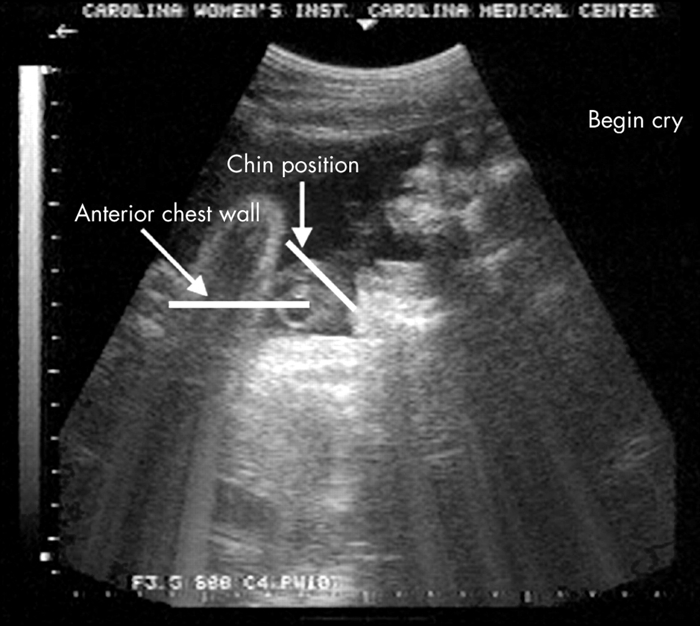

Ултразвуковите технологии ни разрешават да надникнем в матката и да следим развиването на плода. Така да вземем за пример видео, оповестено през 2005 година в Archives of Disease in Childhood – Fetal and Neonatal Edition, демонстрира, че 33-седмичен зародиш прави лицеви изражения, които на ултразвуковия профил наподобяват на рев.

След като подтикват плода посредством осцилация и тон, той отваря необятно уста, придърпва брадичката си обратно и издава три огромни поредни въздишки (гръдният му панер се издува, а главата му се накланя назад). Накрая брадичката му потреперва лекичко. Това придвижване е следено при 10 зародиша (около 6% от сканираните бебета).

Признаци на рев, открити в изследването от 2005 година Източник: Gingras et al., ADC Fetal and Neonatal, 2005